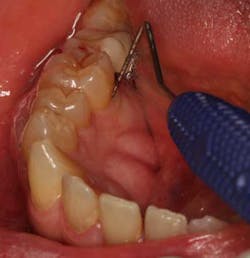

To achieve predictable periodontal therapy results, a guided bone/tissue regeneration procedure (GTR/GBR) is indicated that includes the use of bone-grafting products (e.g., enamel matrix derivative) to regenerate the lost tissue and, most importantly, the bone. (5-8)